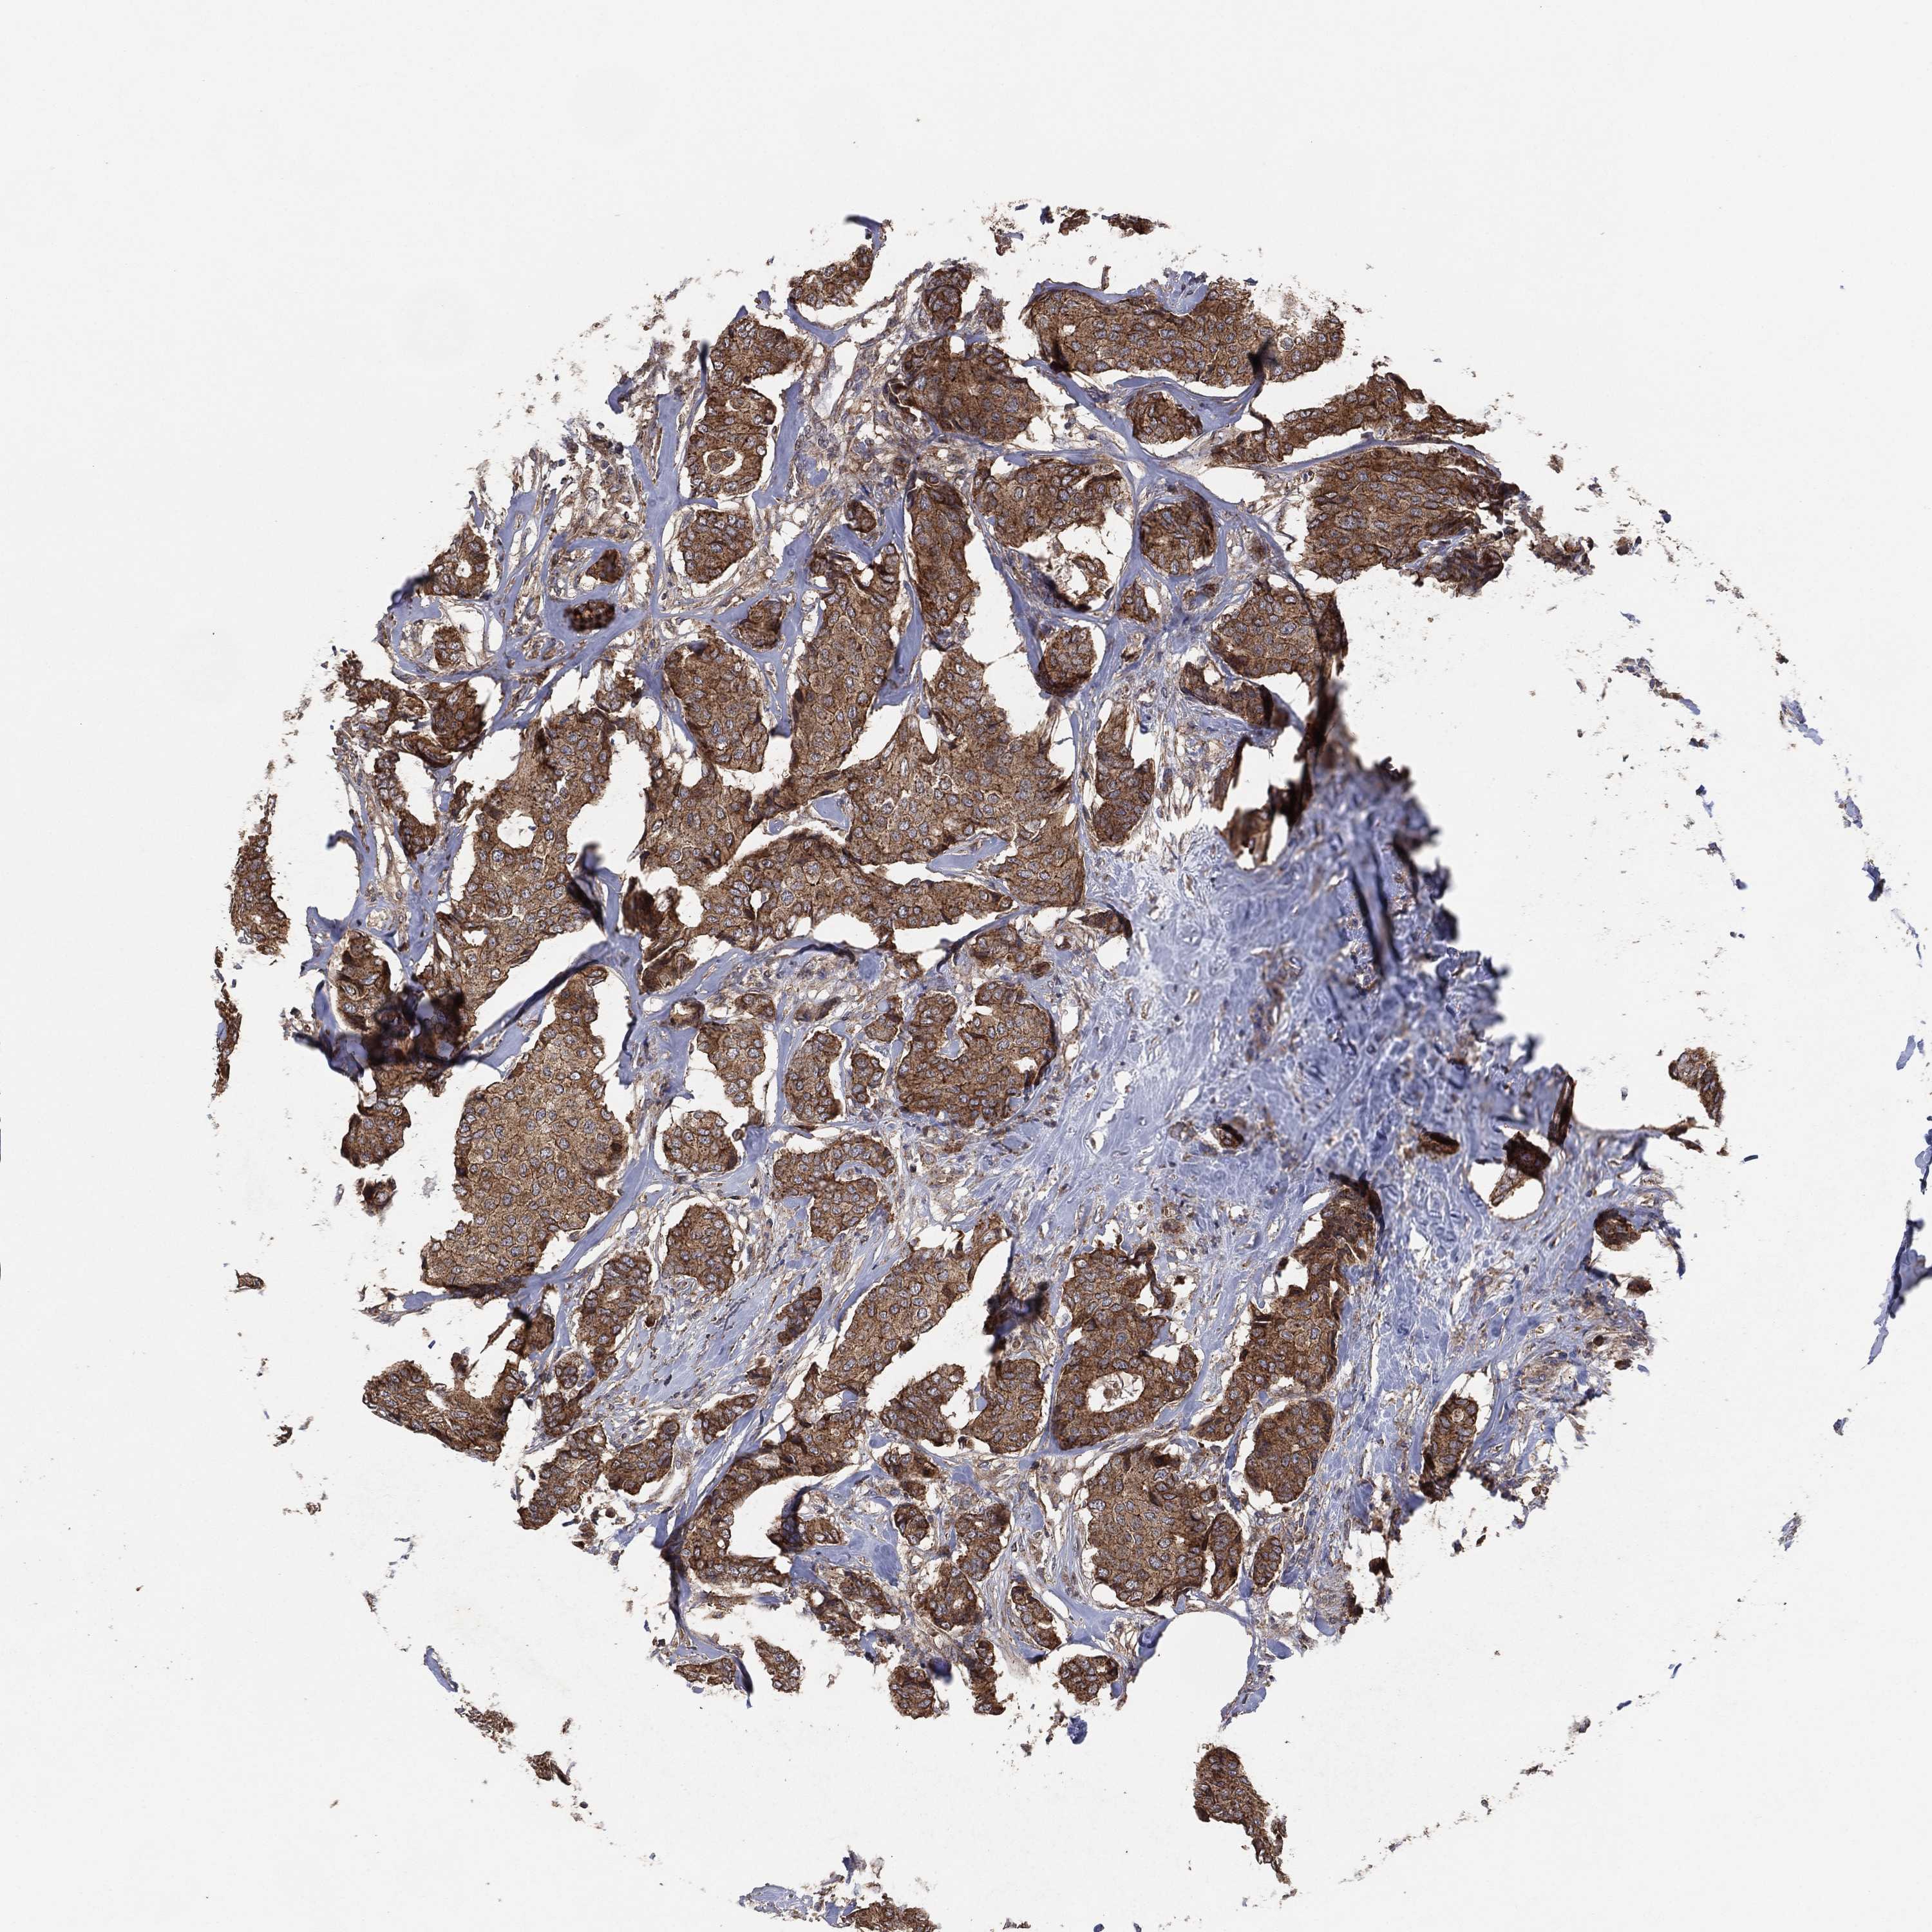

CANCER BREAST CANCER Show tissue menu

BRCA TCGA BRCA VALIDATION PROTEIN EXPRESSION